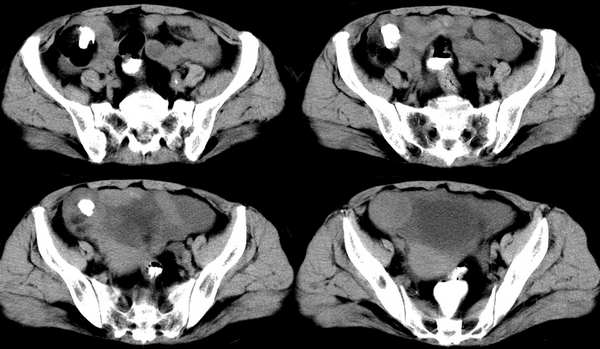

女,59岁,憋气、下腹不适一个月。胸透:双侧大量胸腔积液,反复抽胸水化验为漏出液。彩超示:盆腔占位

右侧卵巢区囊实性占位性病变,内见高密度及囊性脂肪密度,实性部分强化明显,囊性部分未见强化,结合病史多考虑:右侧卵巢恶性畸胎瘤。

请问病人是检查前口服了造影剂还是经肛门灌的,能说明吗

说明:病人检查前4小时口服的造影剂

那高密度是病人喝的造影剂?楼主的意思是那团东西是肠管吗?

那高密度是病人喝的造影剂?周围低密度ct值是多少